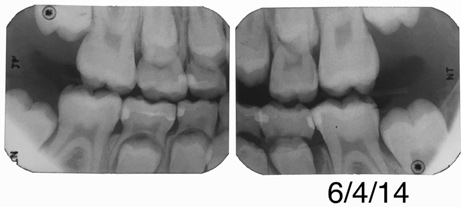

Figure 15 shows bitewings of an 11-year-old boy with high caries risk and history of proximal "kissing lesions" on his primary molars in all four quadrants. He then presented with incipient lesions in his permanent teeth. After resin infiltration (Figure 16), results have been stable for 2 years.

Fig 15. Bitewing of an 11-year-old boy.

Figure 15

Fig 16. Same patient several months later.

Figure 16